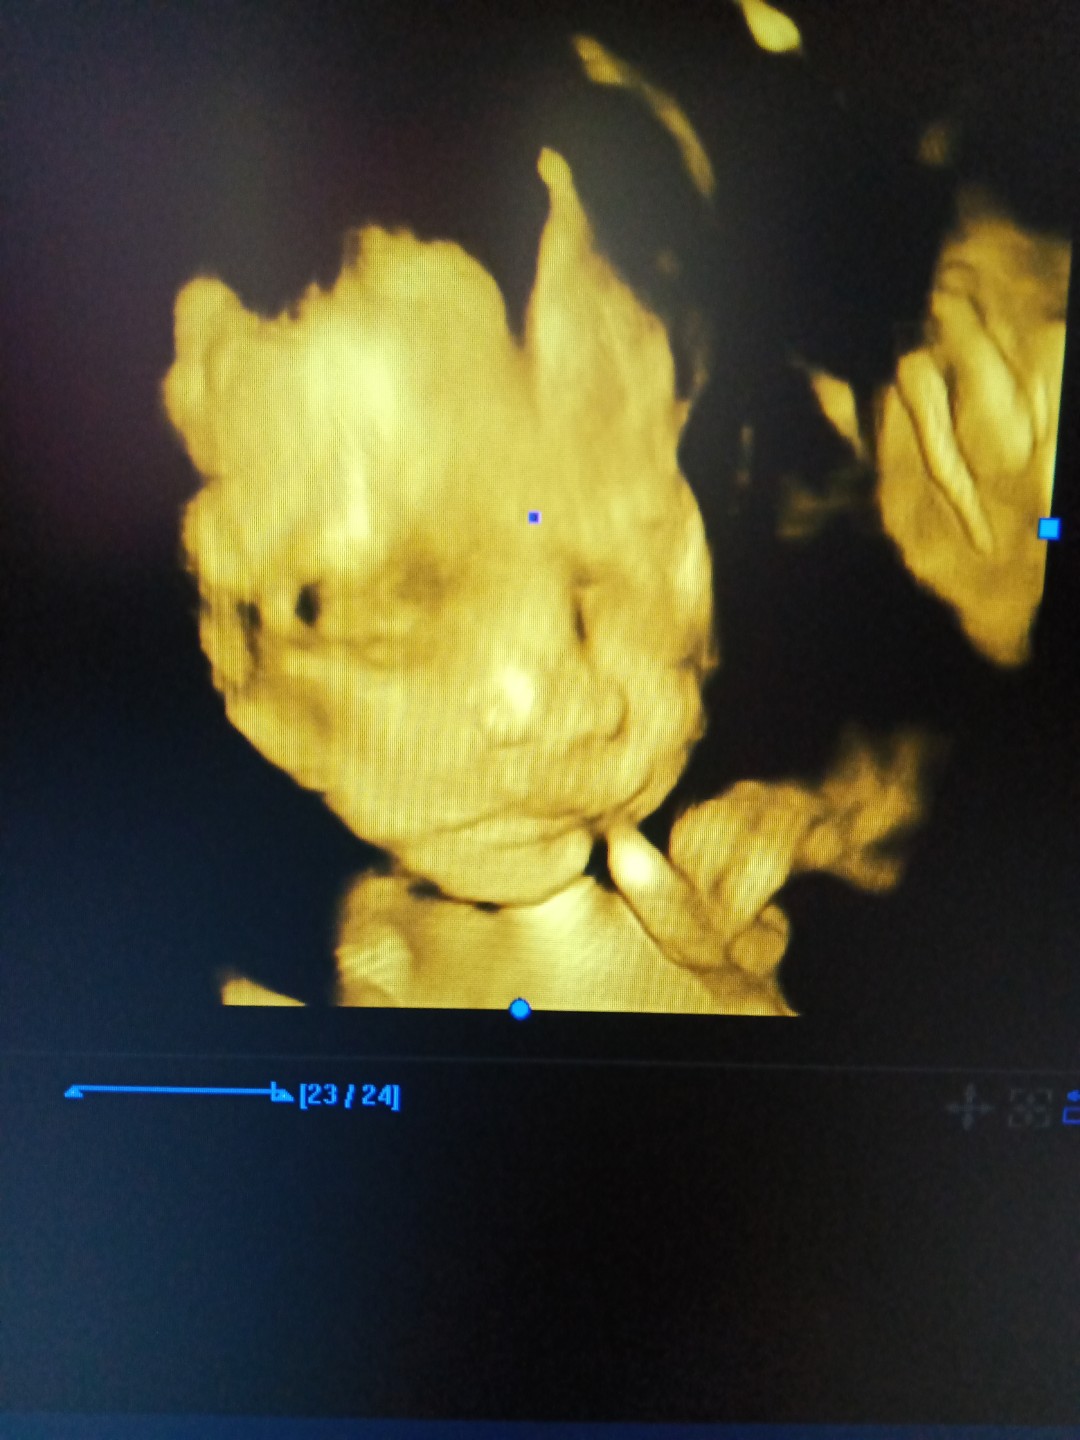

ซาวด์ตอน 34 วีค ผู้สาวจ้า แม่อยากจุ๊บแก้มมาก